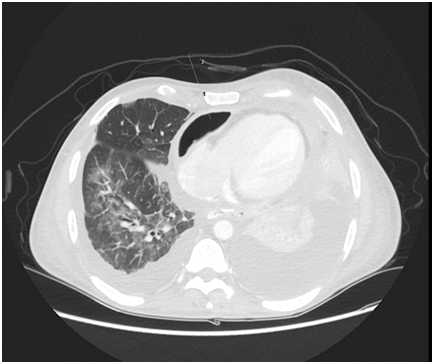

On initial examination, the patient was found to have borderline BP (SBP 101, DBP 60), diminished air entry at the bilateral right and left inferior lung fields. The cardiac examination was remarkable for normal S1, S2 and distended jugular venous distension of 10cm. Chest radiography (CXR) showed an intact esophageal stent along with radiolucent rim surrounding the cardiac silhouette (Figure 1). Echocardiogram (echo) revealed an air gap sign echoic dense space at the anterior and basal part of the heart consistent with the pneumopericardium with no signs of tamponade (Figure 2).  Computed tomography (CT) scan chest confirmed the presence of pneumopericardium in anterior pericardium along with left sided mediastinal pocket of air with foci of gas above the esophageal stent likely communicating with the pericardium (Figure 3). Given the clinical and radiological evidence of the symptomatic large pneumopericardium, we consented the patient on an emergency pericardiocentesis. Goals of care were discussed with the patient and his family and the patient opted interventional care measures. A following pericardiocentesis (with off label CT guidance) right sided parasternal approach (marked at the right 5th intercostal space with angulated entry projection of 70 degree medially with 27mm depth) was performed successfully with aspiration of 70ml of air followed with frothy blood-stained aspirate. The gentleman symptoms resolved immediately with picked up BP (SBP 123,DBP 67) and pigtail kept and secured in place for 5days without any complications.  Thereafter, a follow up echo and CT scan repeated and showed bright improvement in the clinical status (Figures 4 & 5) respectively.

Figure 3 CT axial cut shows anterior Pneumopericardium with proposed entry point at the right 5th Inter Costal Space with medial inclination of 70 degree and 27 mm to reach PE.